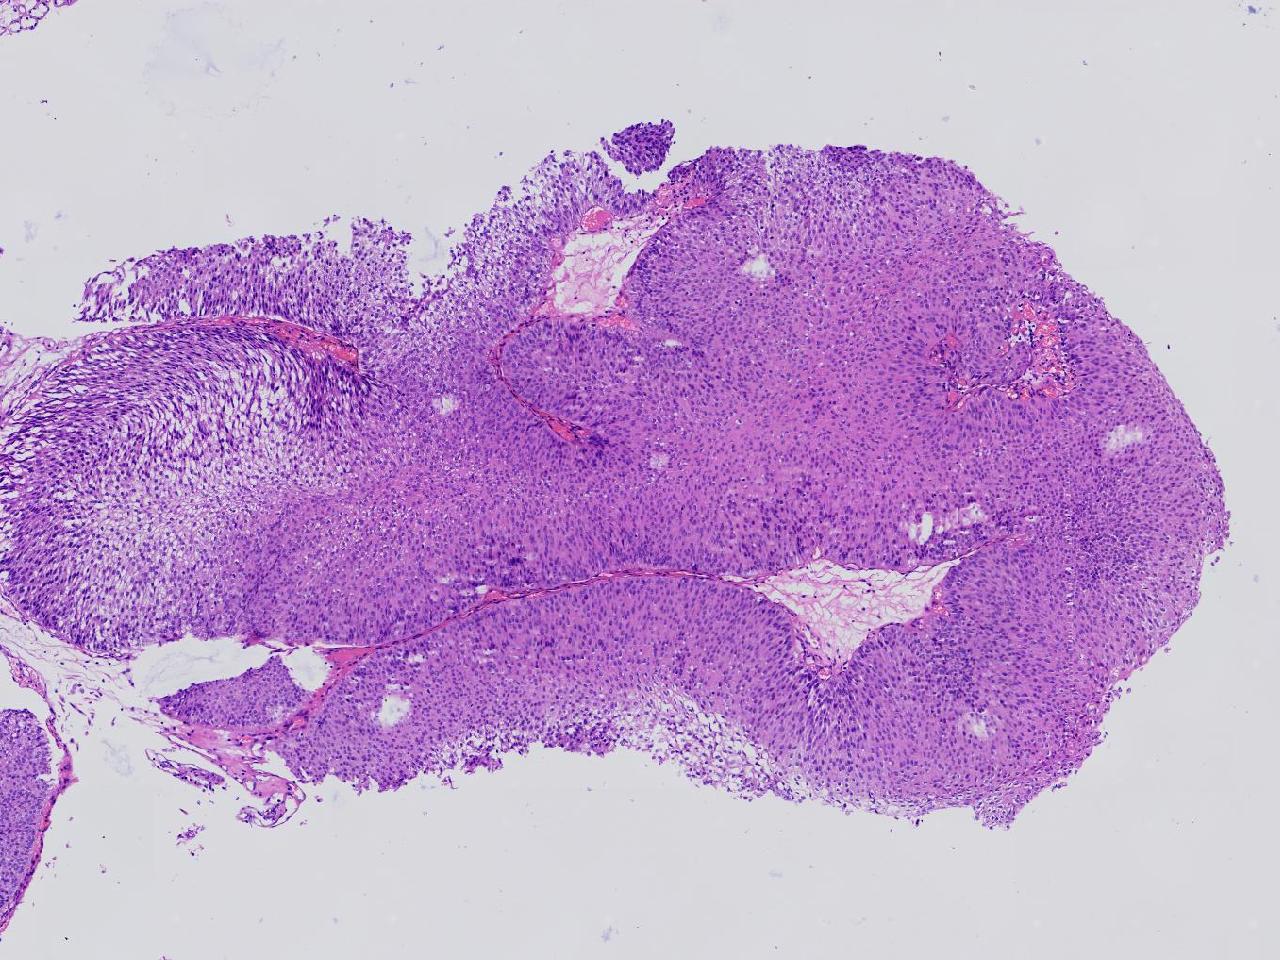

男,79岁,膀胱肿物。

膀胱肿物

灰白色不整形软组织多块,2X1X1厘米。

考虑:乳头状尿路上皮癌

乳头状尿路上皮癌,低级别。

这几张图片上没有看到明确的浸润。